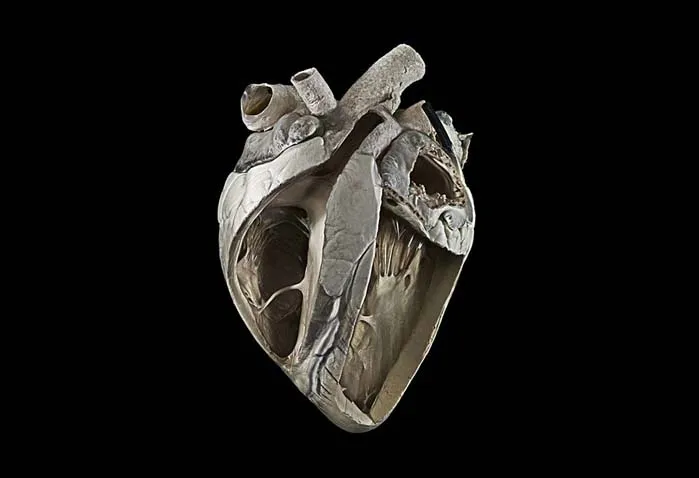

قلب گاو

این تصویر خیرهکننده است چون به شکل یک مجسمهی سه بعدی به نظر میرسد؛ مخصوصا وقتی بفهمیم که قلب واقعی به عنوان یک نمونه در یک ظرف شیشهای نگهداری میشود. عکاس با نورپردازی زیبا و مهارت بالا از این نمونهی تاریخی تصویربرداری کرده و به آن حیات بخشیده است. سطح خارجی و ساختار داخلی قلب به وضوح در این تصویر قابل مشاهده است. اندازهی قلب این گاو چهار برابر قلب یک انسان است.